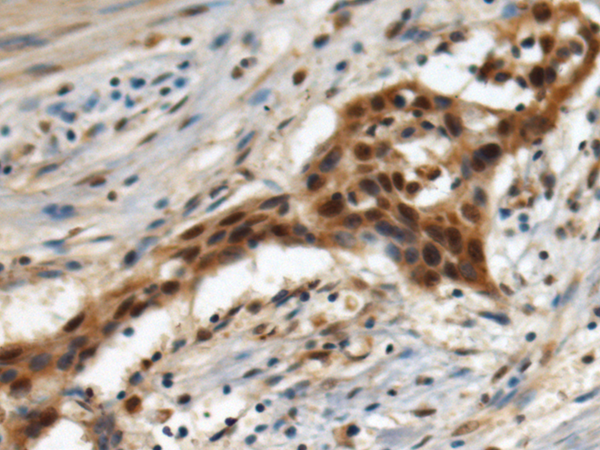

IHC positive control: |

Human esophagus cancer |

IHC Recommend dilution: |

100-300 |